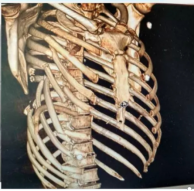

01 肋骨/胸骨骨折的精准治疗

手术内固定术:采用钛合金接骨板、记忆合金环抱器等先进材料,对多发性肋骨骨折、连枷胸(浮动胸壁)进行稳定固定,显著缓解疼痛、改善呼吸功能。